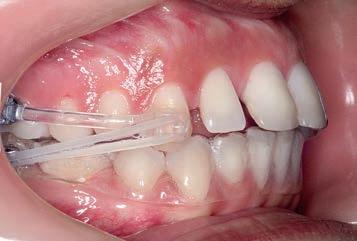

Treatment commenced with the Motion Clear Class II appliance bonded directly to the upper canines and first molars with 6 oz, ¼ intraoral elastics for the first month and 8 oz, 3/16 elastics for the second and third months, engaged for Class II traction to molar tubes bonded to the lower second molars. An Essix .04 vacuum-formed retainer was employed in the lower arch for maximum anchorage.

By the end of the first month of sagittal correction, there was already evidence of some derotation of the upper first molar and movement of the buccal segment (molars, premolars and canines) toward a Class I occlusion. Space was also beginning to open between the upper incisors. After